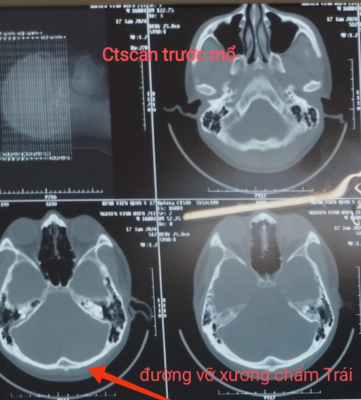

Hình 2. Hình ảnh đường vỡ xương chẩm, máu tụ trong mổ

Kết quả trên phim cắt lớp vi tính: vỡ xương chẩm, MTNMC hố sọ sau bên Trái, gây chèn ép tiểu não, bề dày khối máu tụ khoảng 17mm.

4.1. Xquang: có thể thấy đường vỡ xương chẩm trên Xquang, tổn thương xương kết hợp.

– Hình ảnh các tổn thương xương (vỡ xương chẩm). tổn thương nhu mô não ( dập não, tụ máu dưới màng cứng, trong nhu mô não…), chèn ép não thất 4.